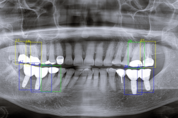

경희대학교치과대학 치주과학교실(주임교수 신승일)이 주최하고 경희 치주임플란트연구회(회장 허인식)가 후원한 제11회 경희대학교 치주과 종합학술대회(K-PERIO 2025)가 지난 20일 서울 코엑스 컨퍼런스룸에서 개최됐다. ‘10+1, K-style 치주와 임플란트를 논하다’를 주제로 열린 이번 대회는 지난 10년간의 학술 축적을 돌아보고 새로운 10년을 향한 비전을 모색하는 자리로 마련돼 개원의·교수·전공의 등 400여 명이 참석했다. 행사는 402호 메인 세션과 403호 K-PERIO Style 세션으로 나뉘어 진행됐다. 메인 세션에서는 임플란트 주위염의 복합 병인을 토대로 비외과적 관리 전략을 제시한 최상훈 원장, 연조직 수술을 5단계 포인트로 정리해 임상 적용도를 높인 한호철 원장, 각화점막의 필요성과 치료 전략을 문헌과 근거 중심으로 정리한 임현창 교수의 강연이 이어졌다. 허인식 회장은 20년 임상 데이터를 근거로 치조제 보존술의 적응증과 장기적 안정성을 제시했으며, 박원배 원장은 상악동 골이식에서의 합병증 사례를 토대로 예측 가능한 수술 전략을 다뤘다. 이어 창동욱 원장이 흡수성 멤브레인을 활용한 GBR 기법을, 박병규 원장이 티타늄 메쉬 기반 GB